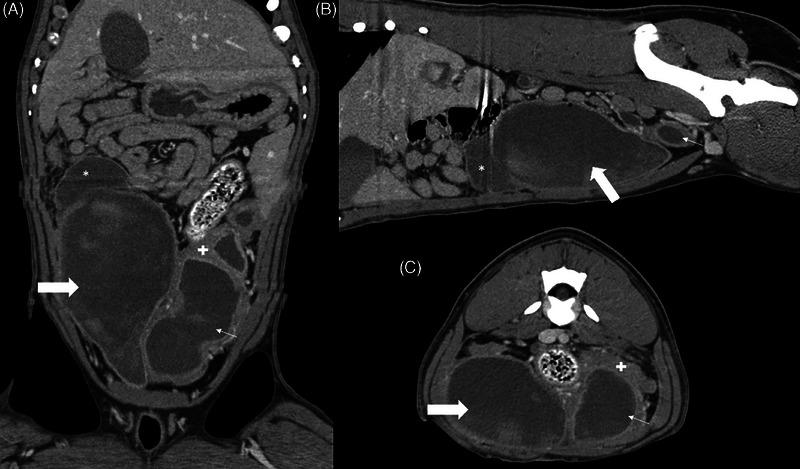

A young, intact, female, American Bulldog was presented for hemorrhagic vaginal discharge. Anemia, thrombocytopenia, leukocytosis with neutrophilia, azotemia, and electrolyte disturbances were detected in the bloodwork. A urachal diverticulum with concurrent uterine distention was identified by ultrasonography and CT. The diverticulum was excised in surgery, and an ovariohysterectomy was performed. Histopathological examination confirmed an abscessed bladder wall with concurrent pyometra.

一只年轻、未绝育的雌性美国斗牛犬因阴道出血性分泌物前来就诊。血液检查发现贫血、血小板减少、白细胞增多伴中性粒细胞增多、氮质血症和电解质紊乱。超声检查和CT检查发现一个脐尿管憩室并发子宫扩张。手术中切除了憩室,并进行了卵巢子宫切除术。组织病理学检查证实膀胱壁脓肿并发子宫蓄脓。